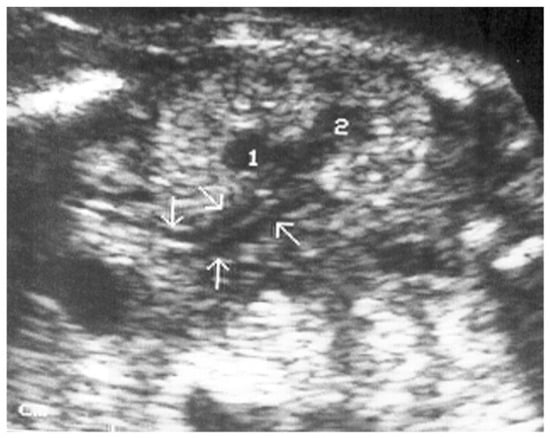

- Abuhamad, A.Z.; Horton, C.E.; Horton, S.H.; Evans, A.T. Renal duplication anomalies in the fetus: Clues for prenatal diagnosis. Ultrasound Obstet. Gynecol. 1996, 7, 174–177. [Google Scholar] [CrossRef]

- Jeffrey, R.B.; Laing, F.C.; Wing, V.W.; Hoddick, W. Sonography of the fetal duplex kidney. Radiology 1984, 153, 123–124. [Google Scholar] [CrossRef]